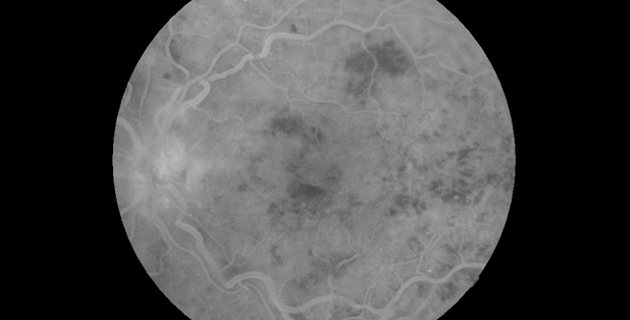

Retinaler Venenverschluss

Eine Zentralvenenthrombose oder eine Venenastthrombose ist ein Verschluss des zentralen blutableitenden Gefäßes des Auges oder eines seiner Äste. Folge ist in erster Linie eine schmerzlose Verschlechterung der Sehkraft. Bluthochdruck, Diabetes mellitus, Erkrankungen des Herz-Kreislauf-Systems und des Blutes sowie ein erhöhter Augeninnendruck sind Hauptrisikofaktoren.

Mittels Fluoreszenzangiographie und optischer Cohärenztomographie (OCT) lassen sich die einzelnen Formen darstellen und klassifizieren. Die Regulierung eines erhöhten Blutdruckes und die Behandlung von Risikofaktoren wirken sich günstig auf die Prognose aus.